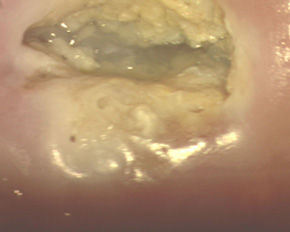

Лікування ерозії шийки матки: пацієнт М